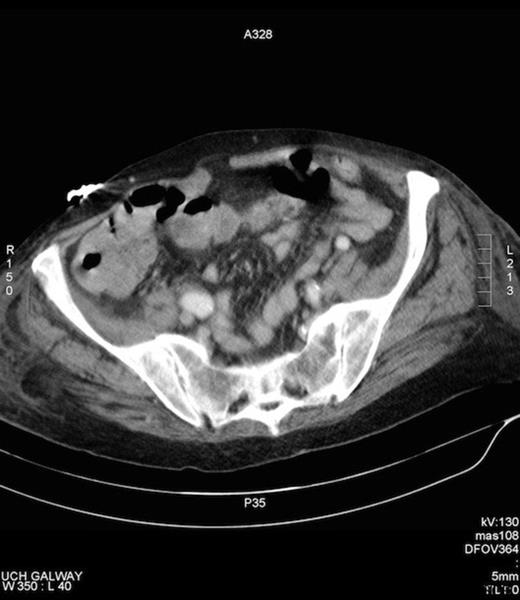

Amyand’s hernia is difficult to diagnose clinically and is rarely diagnosed preoperatively. In a review of 60 cases over a 12 year period only one case was diagnosed pre operatively (7). The difficulty in diagnosis has its origins in the considerable variation of symptoms that patients present with, depending on if the appendix is normal, incarcerated or perforated with the commonest presenting symptom being painful inguinal or inguinoscrotal swelling while the history and examination usually point to an incarcerated hernia (8). Fever and leukocytosis are inconsistent findings. Preoperative CT has revealed the previously unsuspected diagnosis in an occasional report and is useful in establishing the diagnosis early but is not routinely used in clinical situations where a complicated hernia is suspected. Laermann et al illustrated that combining CT with Multi Planar Reconstruction is the most useful technique, to better visualise the appendix and its relationship with surrounding structures, thus aiding in confidently making the correct diagnosis pre-operatively (6). In our case, the appendix could not be visualised, given that the patient has bilateral hip prosthesis, which produced artefact at the level of the appendix. (Figure 4.)

Artefact on CT, secondary to bilateral hip prosthesis, which obscures the appendix.